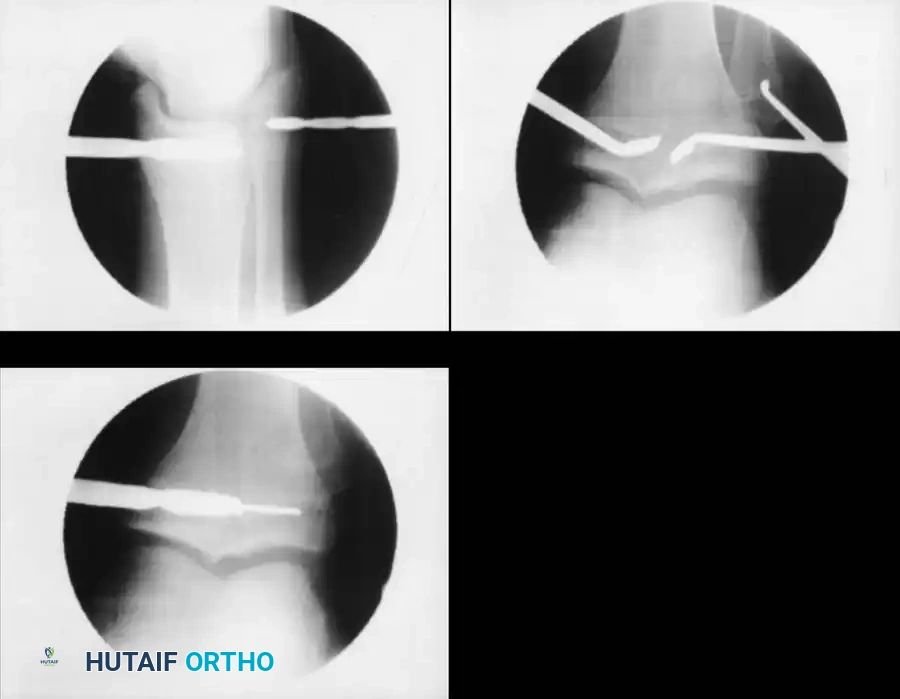

1. Epiphysiodesis

Epiphysiodesis (surgical arrest of the physis) of the longer limb is the procedure of choice for predicted discrepancies of 2 to 5 cm in growing children. It is minimally invasive, carries a low complication rate, and allows for rapid return to full weight-bearing.

Surgical Technique (Percutaneous Approach):

1. Positioning: Supine on a radiolucent table. Fluoroscopy is mandatory.

2. Localization: The physis (distal femur or proximal tibia/fibula) is identified under AP and lateral fluoroscopy.

3. Incision and Drilling: Small medial and lateral incisions are made. A cannulated drill or specialized curette is introduced into the physis.

4. Ablation: The physeal cartilage is systematically destroyed in all quadrants. Care is taken to avoid violating the articular surface or the metaphyseal cortex.

5. Postoperative Protocol: Immediate weight-bearing as tolerated. Return to sports is typically permitted at 4 to 6 weeks once soft tissue healing is complete.